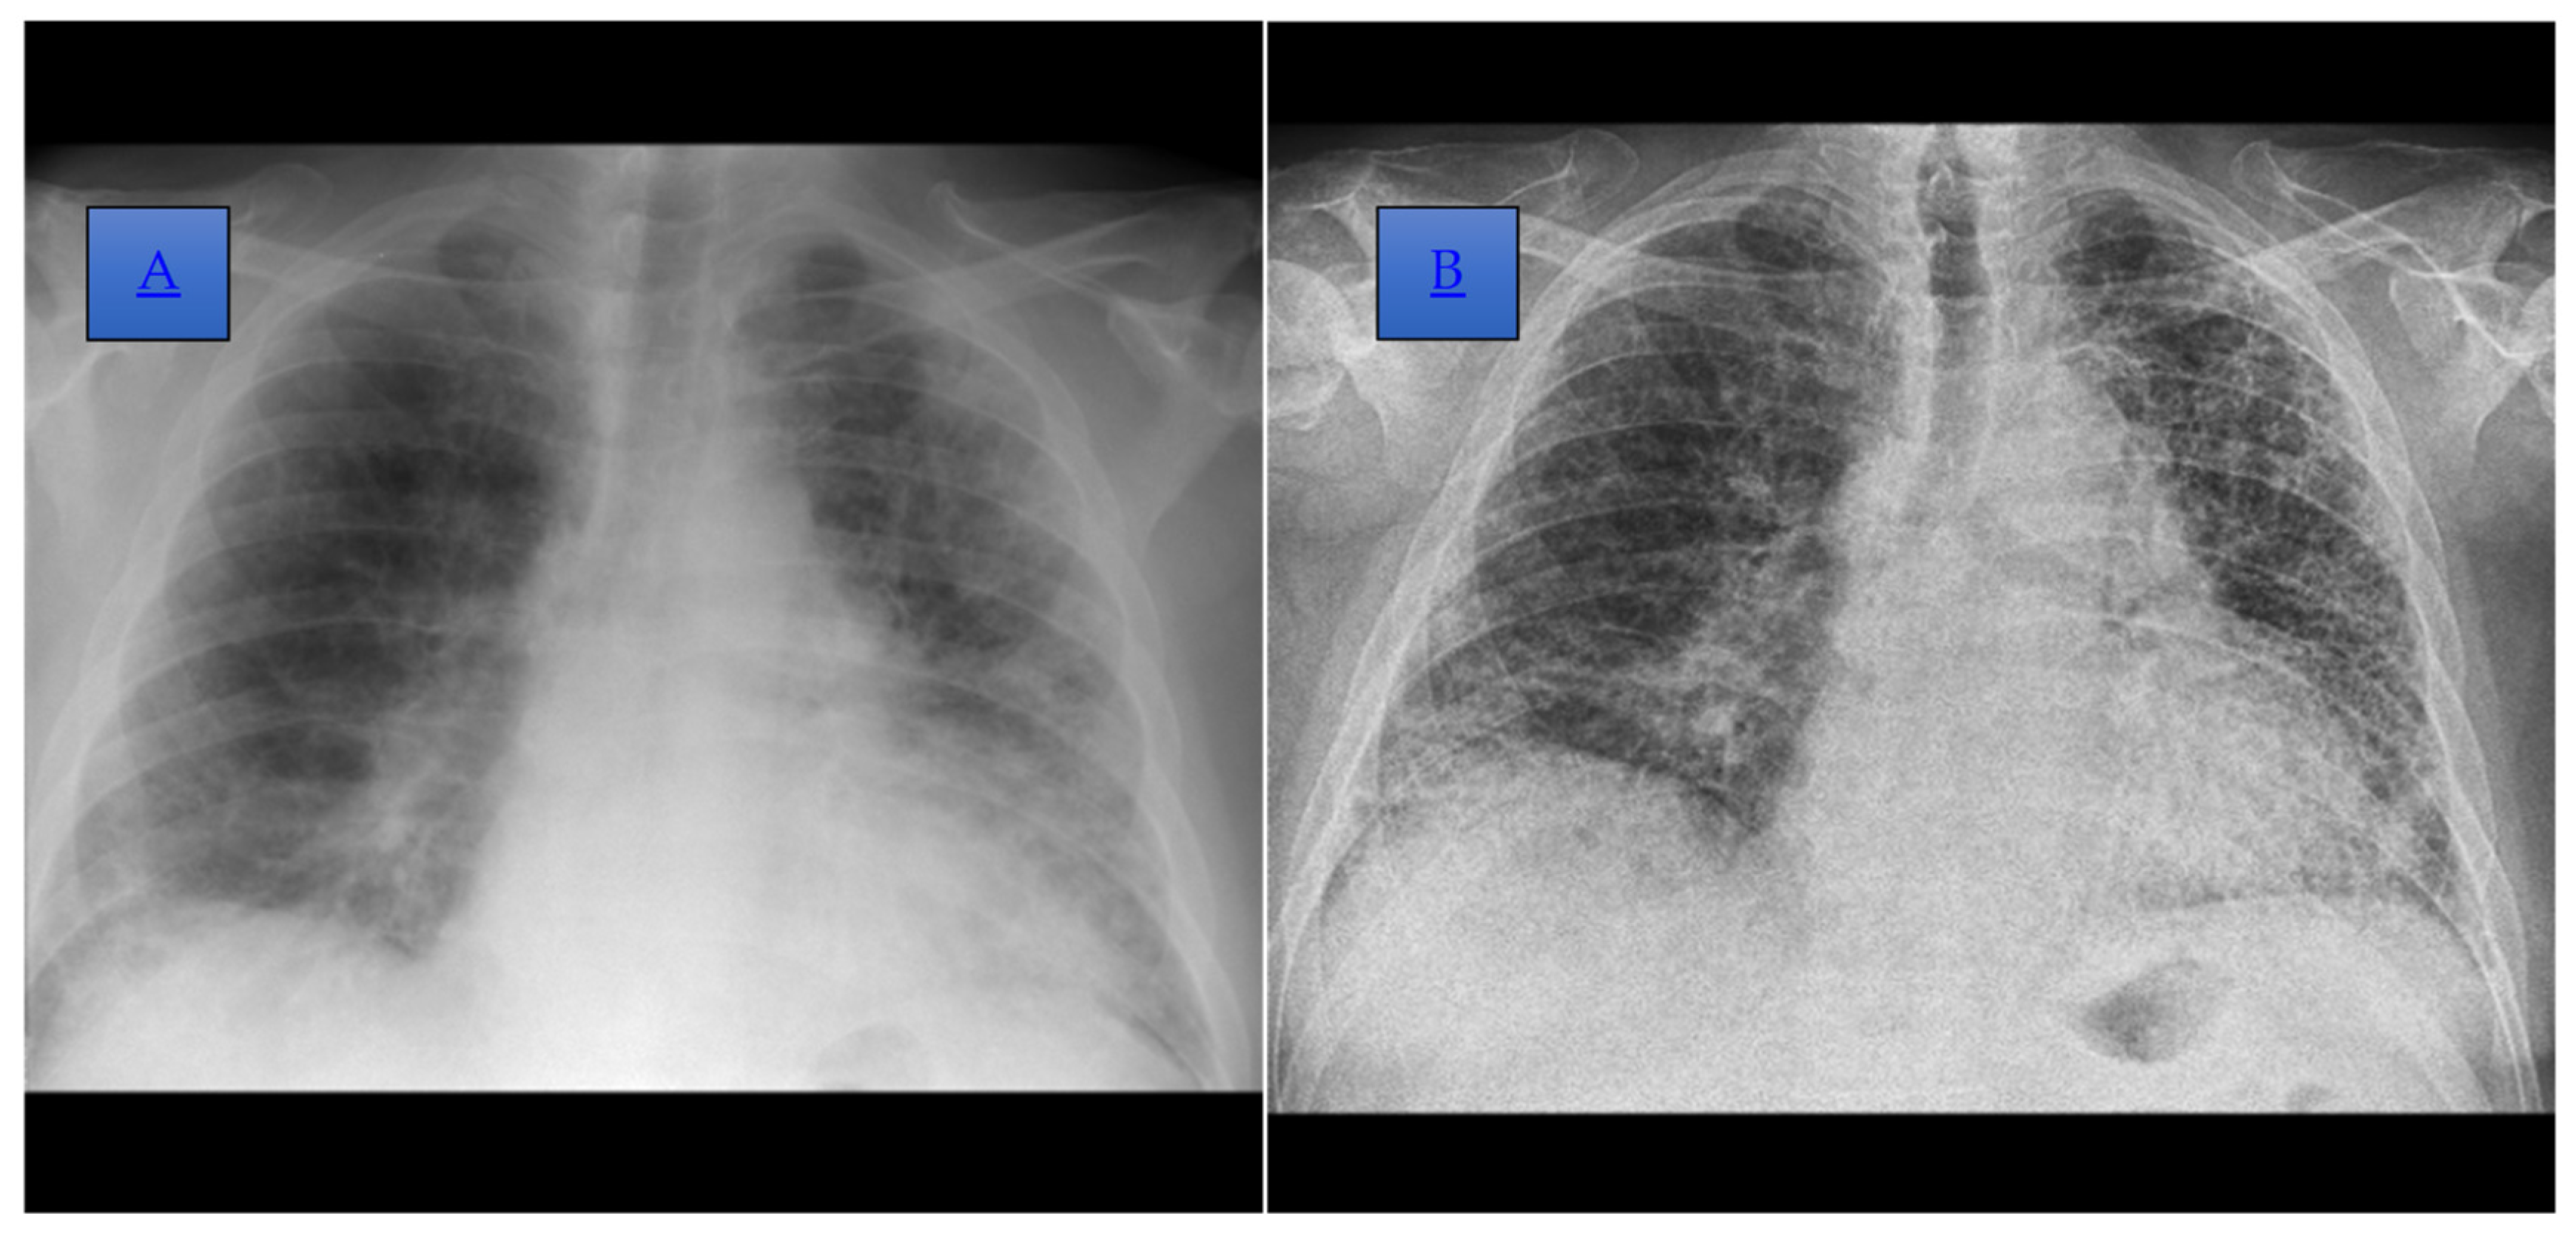

Figure 2. (A) Posteroanterior incidence chest radiograph, performed in 2021, which highlights the accentuation of the bilateral juxtahilar and basal, interstitial, and peribronchovascular pattern, which is more obvious on the left side. A reduction in lung transparency bilaterally, more obviously the left subpleural, is also shown. (B) Posteroanterior incidence chest radiograph, performed in 2022, where an accentuation of the perilobular interstitium with a reticular and pseudo-honeycomb appearance and on the basal right thickening of the pleuritic septa, dispersed in the left 2/3 lobe and the external basal in the right lobe, is shown.